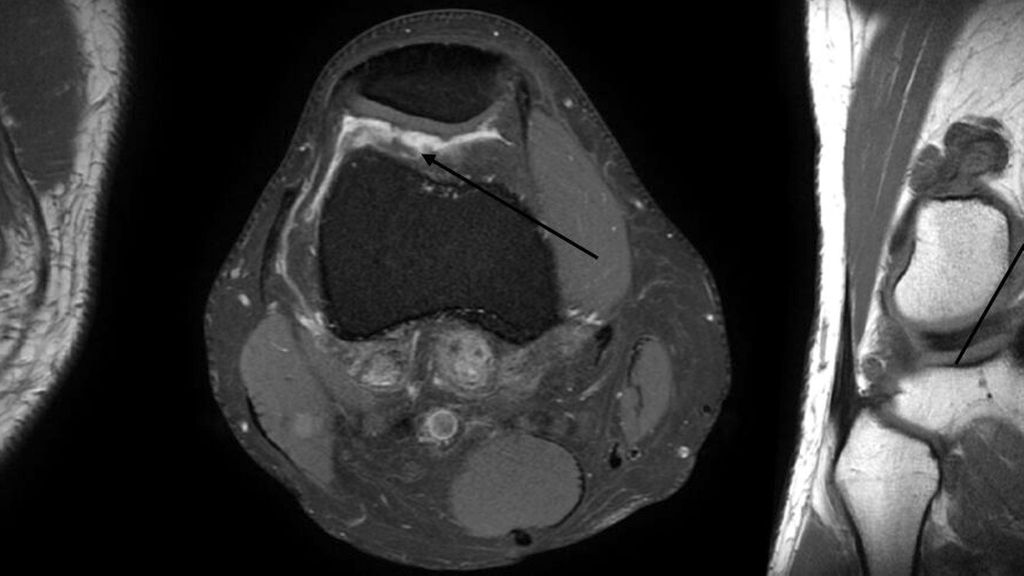

Abb. 1: Klinisch präsentieren sich die Patienten häufig mit wiederkehrenden Schwellungen und Kniegelenksergüssen. Im vorliegenden Fall wurden >80 ml bernsteinfarbenes Punktat abgezogen. Das Punktat wird zur weiteren Befundung an die Bakteriologie, Pathologie und zur Zellzahlzählung delegiert. In den MRT-Bildern ist eine dorsal gelegene PVNS erkennbar (Pfeilmarkierung)